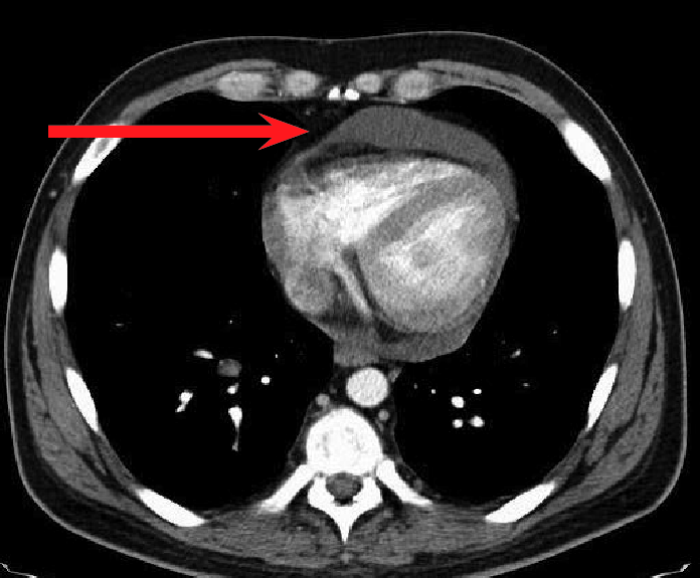

經(jīng)檢查,徐大爺被確診為結(jié)核性心包炎。

“該病起病隱匿,常有心外原發(fā)性結(jié)核病灶或同時有其他漿膜腔結(jié)核性積液存在,易出現(xiàn)長期低熱、盜汗、疲乏無力等癥狀,多無胸痛,易轉(zhuǎn)為慢性,最后形成縮窄性心包炎?!备腥究莆塘亮玲t(yī)生介紹,結(jié)核性心包炎為重癥結(jié)核病之一,對患者生命、生活質(zhì)量均可造成嚴(yán)重影響。

確診結(jié)核性心包炎后需要規(guī)律治療,防止病程進(jìn)展到縮窄階段,降低死亡率。由于徐大爺基礎(chǔ)疾病較多,感染科團(tuán)隊為其量身定制了個體化抗結(jié)核治療方案。